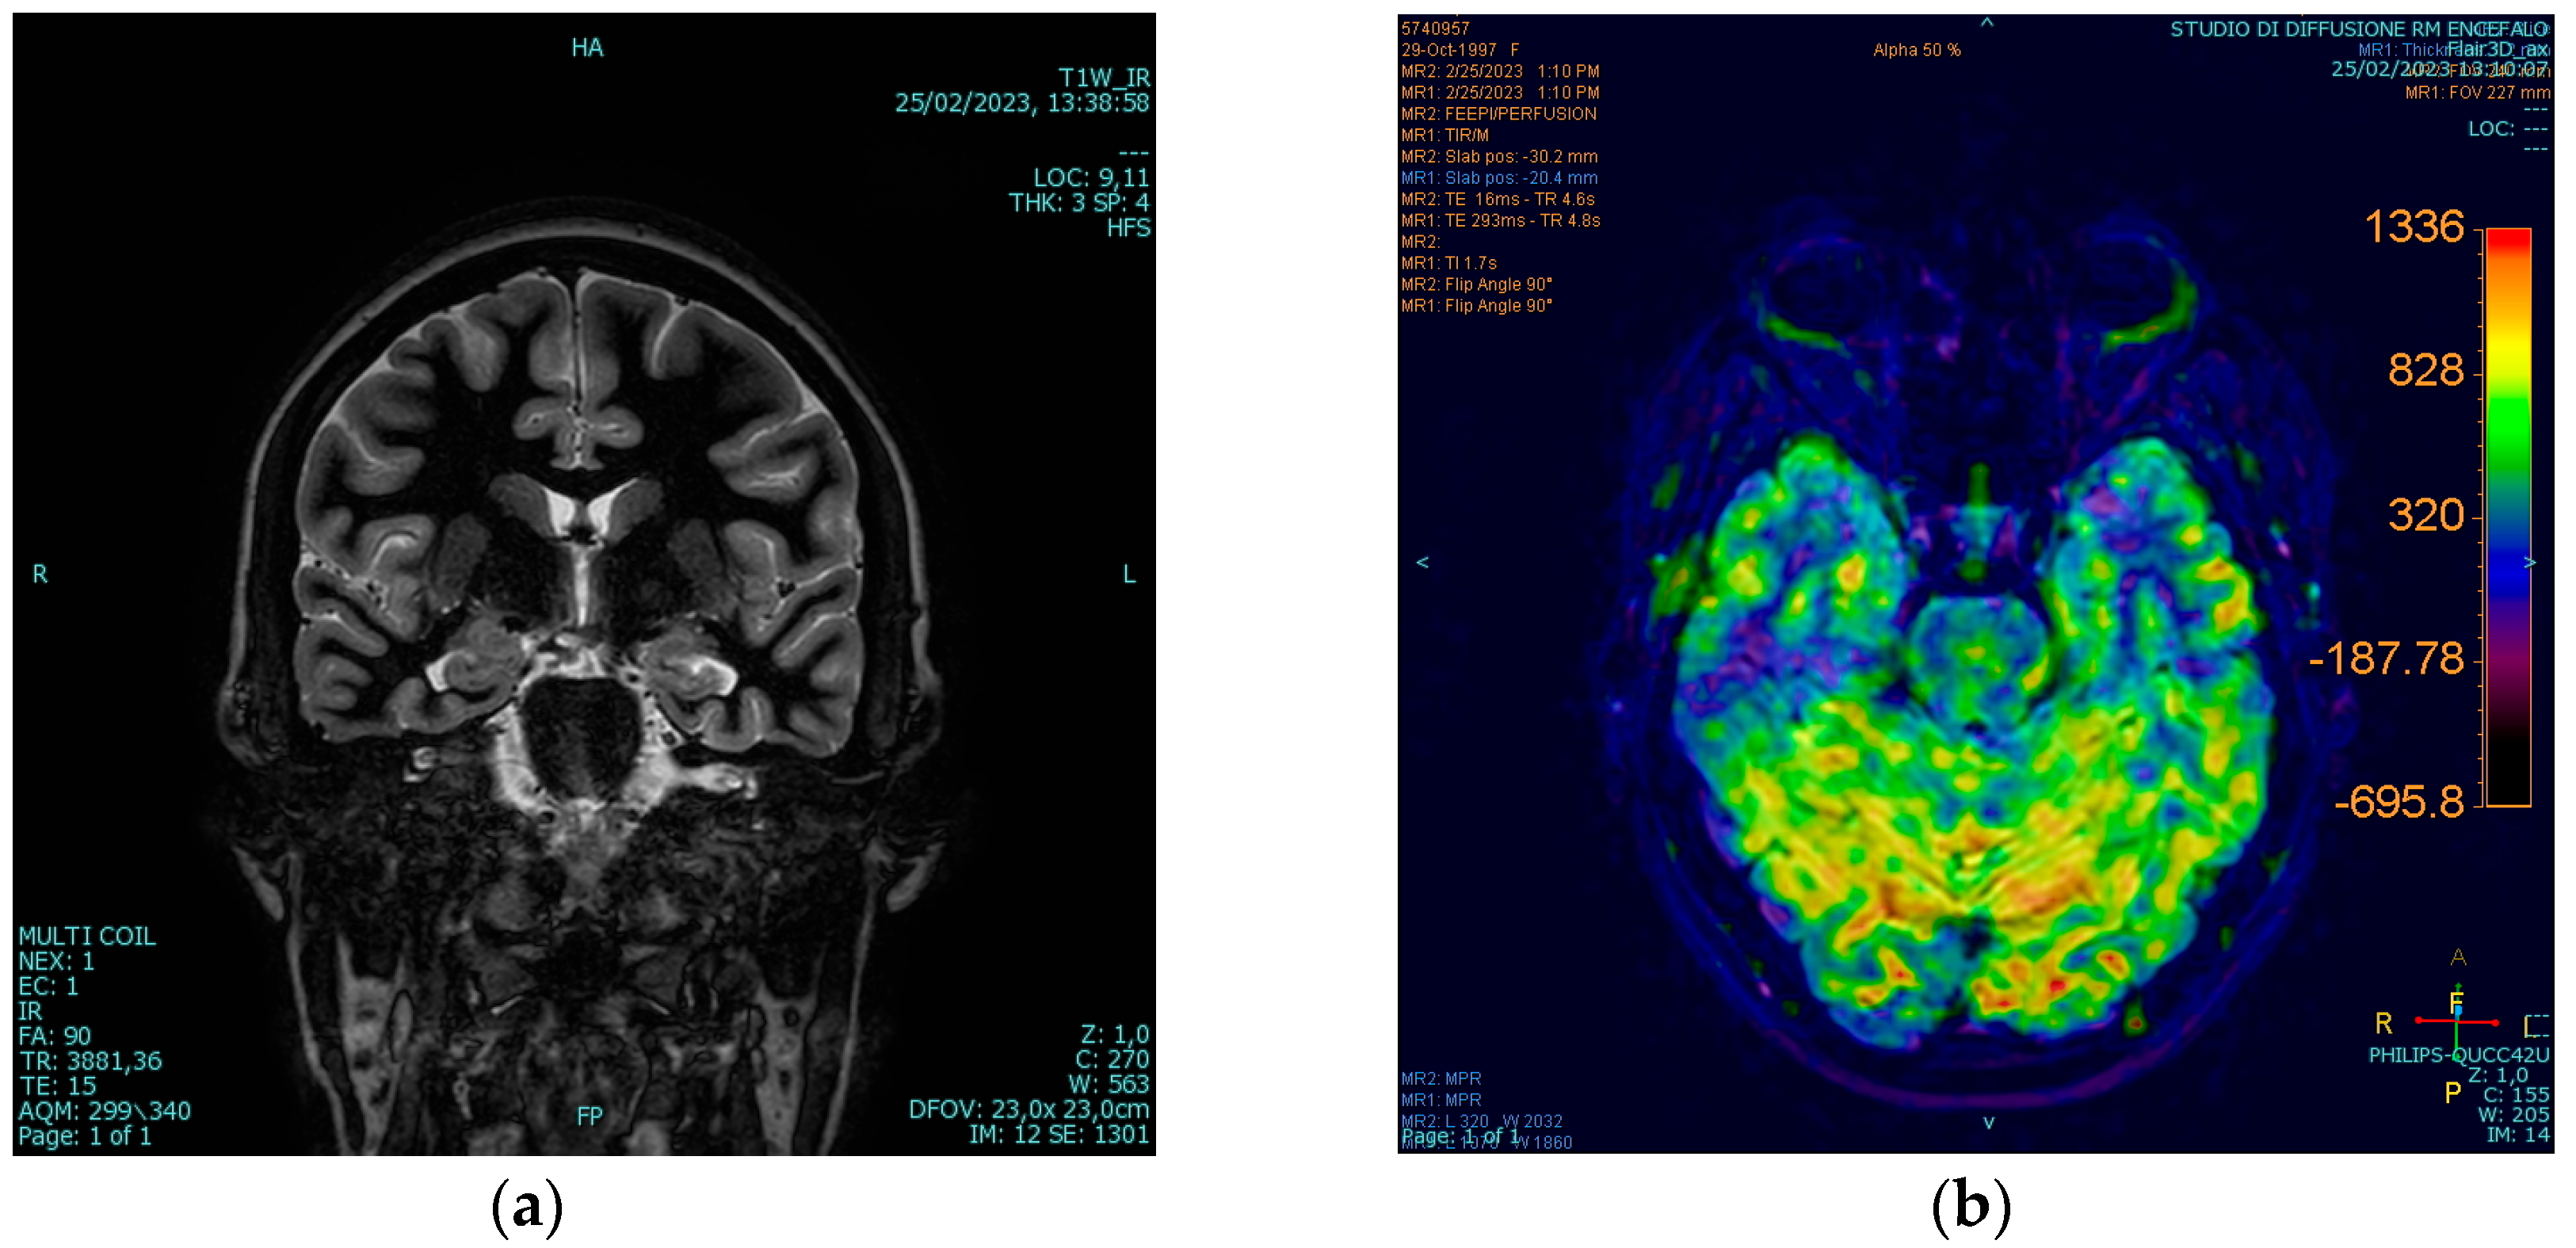

3.4. Diagnosis